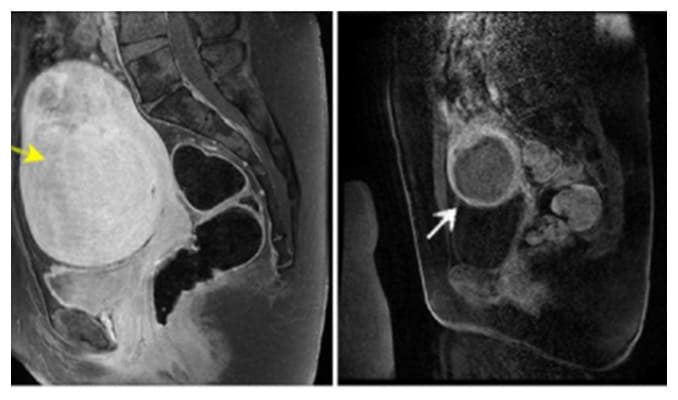

Una de las principales herramientas con las que contamos los ginecologos hoy en dia para detectar los miomas, además del historial de hemorragia menstrual y de dolor, que algunas pacientes pueden presentar, esta el ultrasonido que de rutina se realiza en el consultorio, ya que muchas veces los miomas son asintomáticos.

También se pueden usar estudios como la tomografía o la resonancia sin embargo el ultrasonido tiene una efectividad diagnostica en médicos con experiencia cerca del 100%.